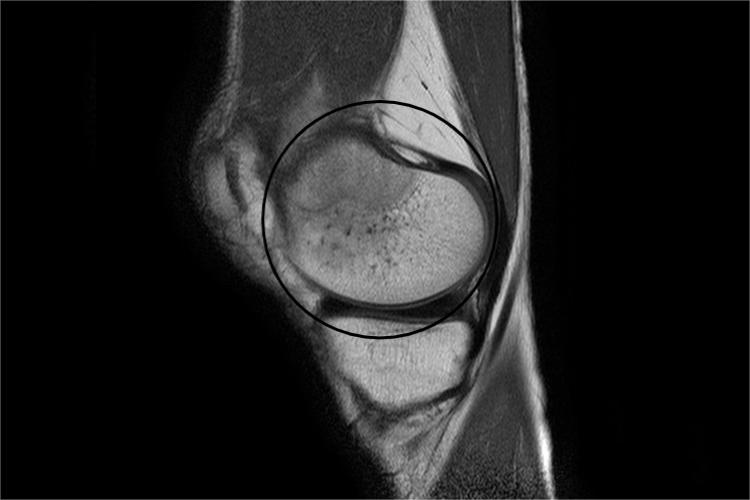

骨软骨瘤是位于骨表面的骨性突起物,顶面有软骨帽,中间有髓腔。患者可长期无症状,会出现骨性包块,若肿瘤压迫周围组织或其表面的滑囊发生炎症,则可产生疼痛、局部麻木、活动受限等。X线可在干骺端见从皮质突向软组织的骨性突起。